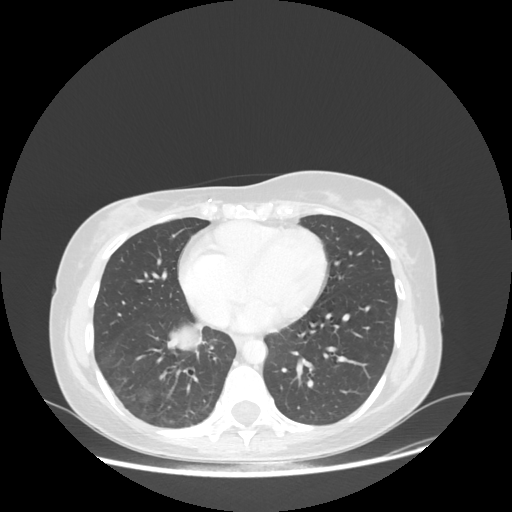

Original NATIVE CT scan (input)

Full window (WL 1023.5, WW 4095 β†’ Low βˆ’1024, High +3071)

Lung window (WL -600, WW 1500 β†’ Low βˆ’1350, High +150)

Mediastinum window (WL 40, WW 400 β†’ Low βˆ’160, High +240)